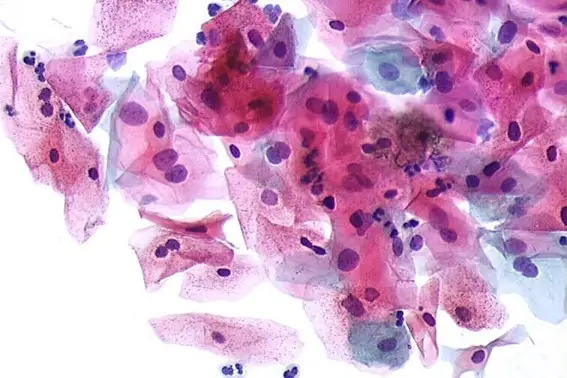

Citologia cérvico-vaginal em meio líquido

Há diversas plataformas de citologia em meio líquido validadas no mercado, as quais possuem diferenças no processamento técnico e na coleta. Em geral, a coleta é muito similar à convencional, podendo ser realizada por meio de espátula e escova cervical ou com dispositivo único: escova combinada que coleta as células da ectocérvice e endocérvice, simultaneamente. A diferença é que o material não será disposto em lâmina, mas colocado no frasco contendo o meio, que além de preservar a morfologia celular tem função fixadora. O laboratório Lapaci utiliza a Metodologia Gynoprep. Através uma filtragem especializada por meio de um filtro de dupla membrana, há uma retenção de interferentes, proporcionando uma amostra mais límpida e concentrada.

– Preparo técnico padronizado com material celular em monocamada facilitando a interpretação e menor tempo de leitura